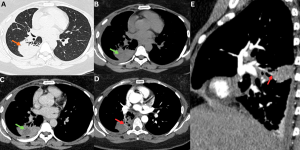

Fig 22: Clinical history:

A known case of disseminated mucormycosis presented with abdominal pain, fever, and acute kidney injury.

Figure A:

Axial HRCT chest image demonstrates both the halo sign (blue arrow) and reverse halo sign (red arrow), consistent with invasive pulmonary fungal infection.

Figures B & C:

Axial and coronal contrast-enhanced CT (CECT) abdomen images demonstrate nonenhancement of the left kidney (green arrow) with severe paucity of contrast opacification in the left renal artery (white arrow). Multiple wedge-shaped nonenhancing areas are noted in the right kidney (yellow arrows), consistent with bilateral renal infarctions. An additional wedge-shaped nonenhancing area is seen in the inferior pole of the spleen (orange arrow), consistent with splenic infarction.